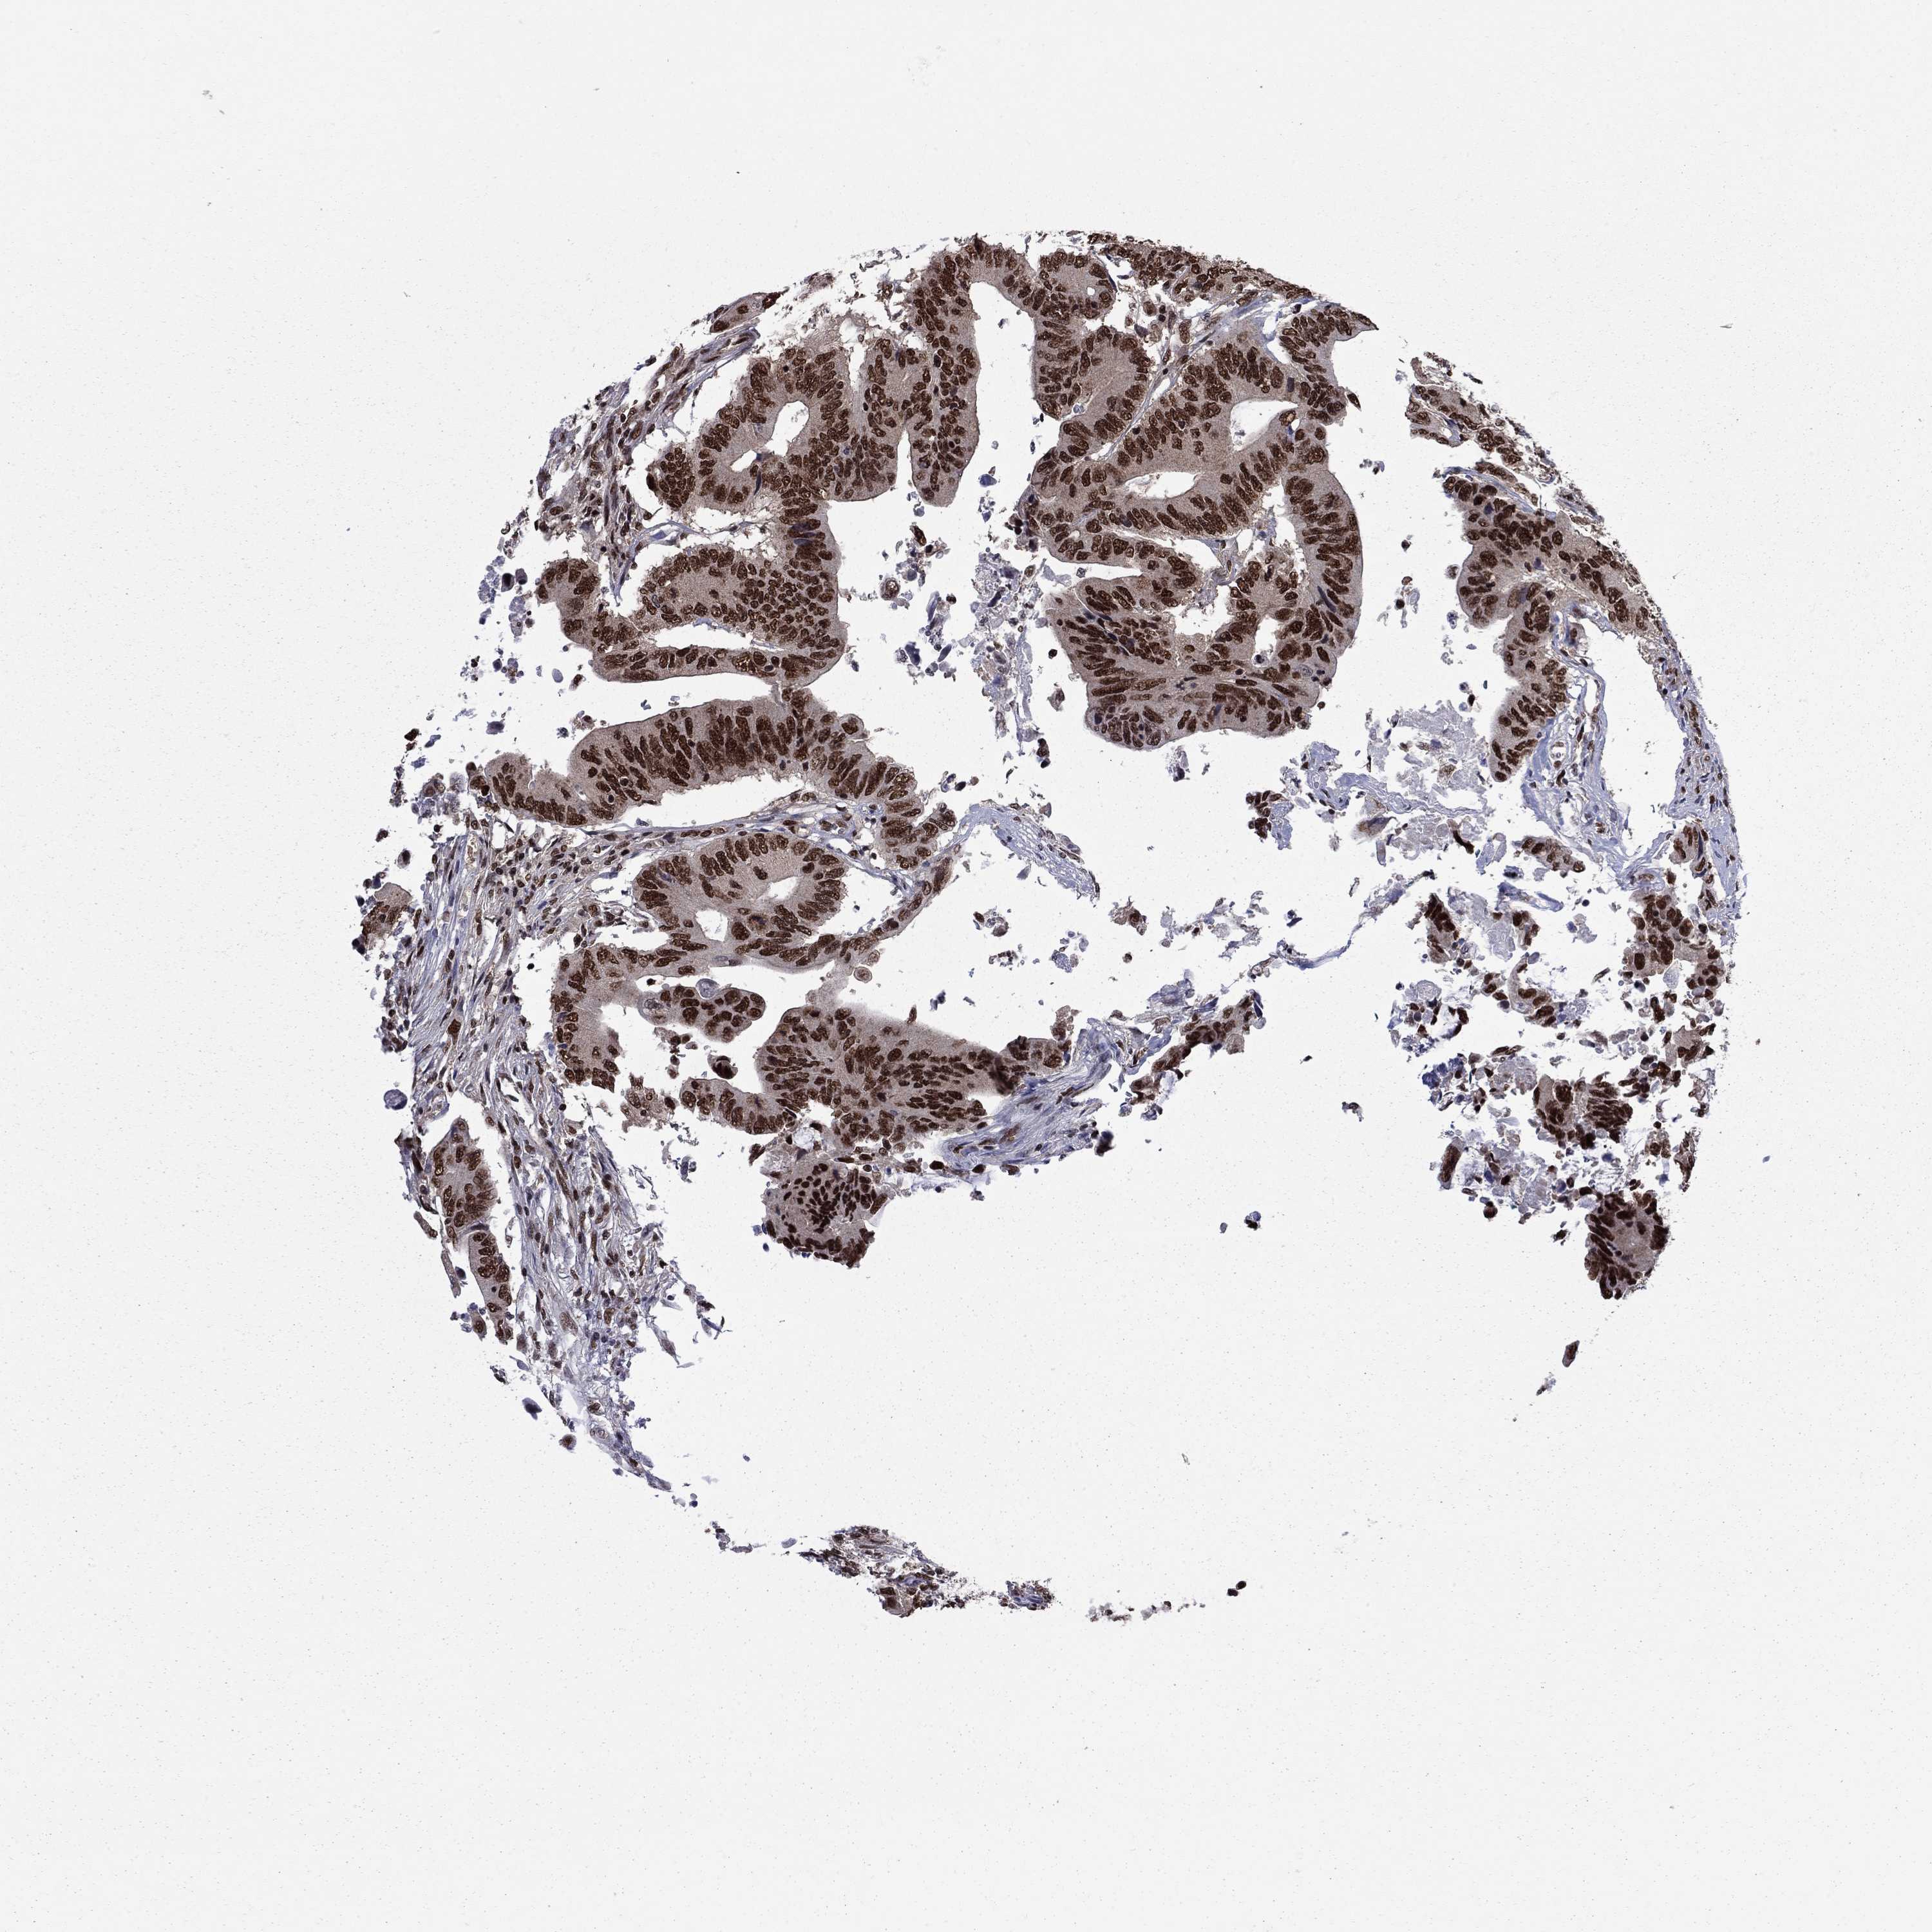

CANCER COLORECTAL CANCER Show tissue menu

Colorectal cancer

Human cancer

Colon adenocarcinoma